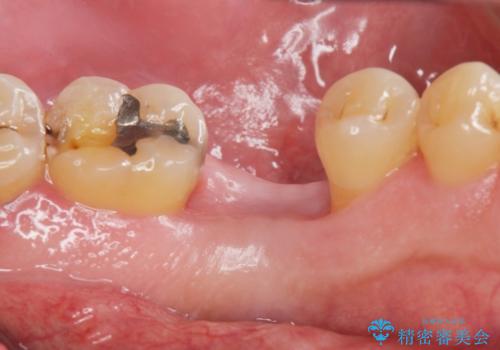

- 奥歯を失ったのち放置してしまった部位にインプラント治療を希望されて来院されました。

インプラン治療は、ブリッジと異なり前後の歯を削る必要がなく、入れ歯と違い取り外しの必要がありません。